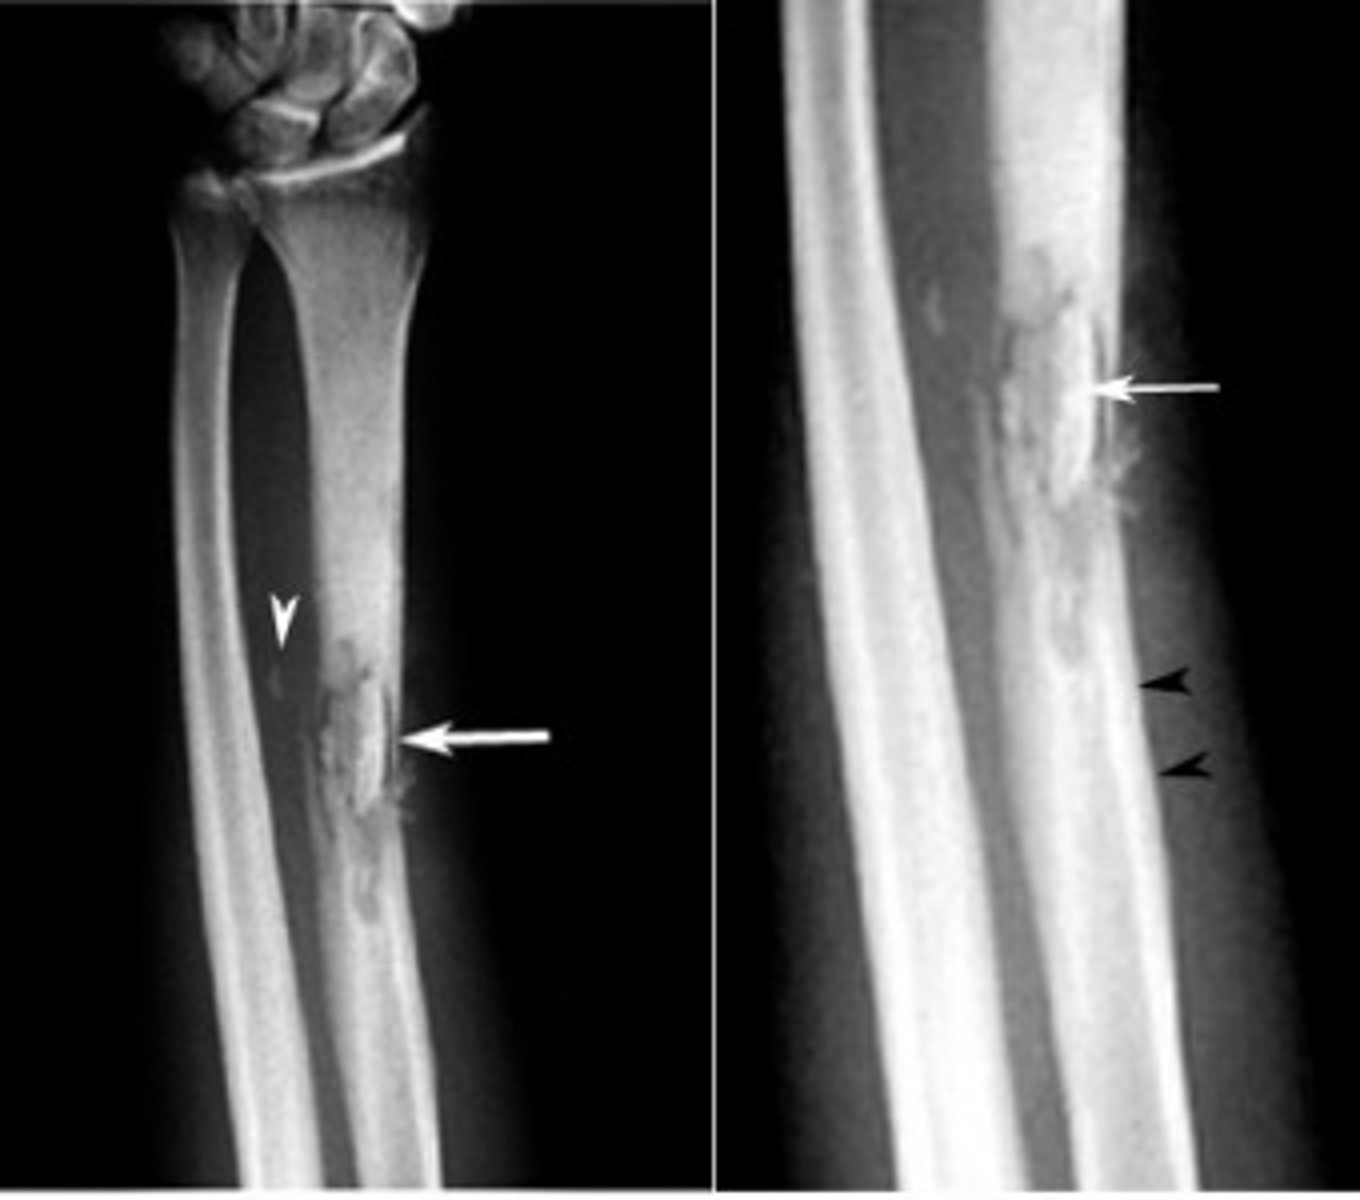

osteomylelitis

Severe infection of the bone, bone marrow, and surrounding soft tissue

Sequestrum

Area of dead bone separates from living bone.

⢠Antibiotics have difficult time reaching sequestrum

⢠Sequestrum needs surgical debridement or sinus tract develops and purulent drainage leaks out

Dx studies for osteomyelitis

⢠Usually don't appear on x-ray for 2 -4 weeks after initial symptoms